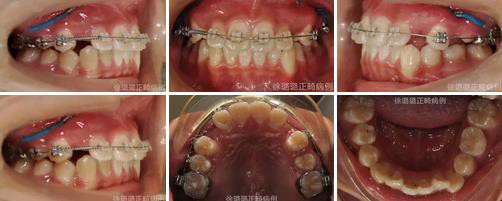

口內(nèi)特征:恒牙早期,雙側(cè)磨牙關(guān)系為輕度遠中關(guān)系,前牙深覆牙合 Ⅱ°,深覆蓋 6mm,上下頜牙弓中線不端正,上頜中線右偏 3mm,上頜前牙唇傾,下頜牙列輕度擁擠,右側(cè)上頜間隙不足,左側(cè)乳尖牙滯留,上頜左側(cè)乳尖牙對刃牙合,上下頜牙弓形態(tài)不對稱。

360截圖20170120124750762.jpg

導(dǎo)萌術(shù)中口內(nèi)像